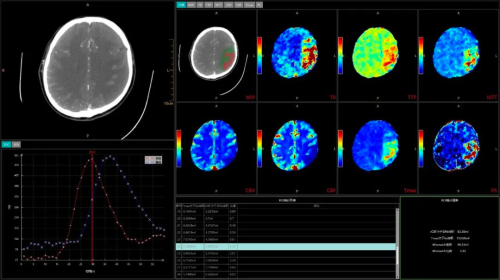

在卒中救治领域,无极系列CT配备的16cm宽体探测器,无需移床即可覆盖全脑,能够快速判断卒中类型。得益于该设备的协议快速切换能力,支持在缺血性脑卒中患者全脑灌注扫描中插入头颈CTA协议,60秒内便能完成全脑CTP+头颈CTA+全脑CTP的一站式扫描,一次操作即可采集全脑灌注数据及头颈CTA图像,获取包括脑实质解剖成像、脑血管及脑血流分布在内的全脑信息,大幅缩短了检查时间,让卒中救治分秒必争。

CTP+CTA+CTP一站式卒中扫描

灌注分析+核心梗死区与缺血半暗带量化分析